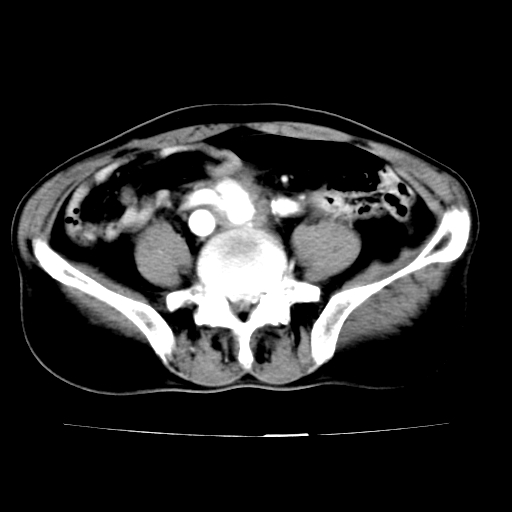

标题: V0243:右髂总动脉瘤附壁血栓形成?破裂?动静脉瘘? [打印本页]

标题: V0243:右髂总动脉瘤附壁血栓形成?破裂?动静脉瘘?

男,75岁,腹痛月余,彩超发现脐周腹主动脉异常回声。临床诊断:腹主动脉瘤。

ct诊断:右骼总动脉囊性动脉瘤并瘤内附壁血栓形成,与下腔静脉之间形成动静脉瘘。

请问各位老师:能排除动脉瘤破裂的可能吗?

各位老师注意到下腔静脉的充盈缺损了吗?注意到动静脉漏了吗?

当时是扫描的标准动脉期,可是下腔静脉与腹主动脉同步强化且幅度一致。所以我想动静脉瘘是存在的。